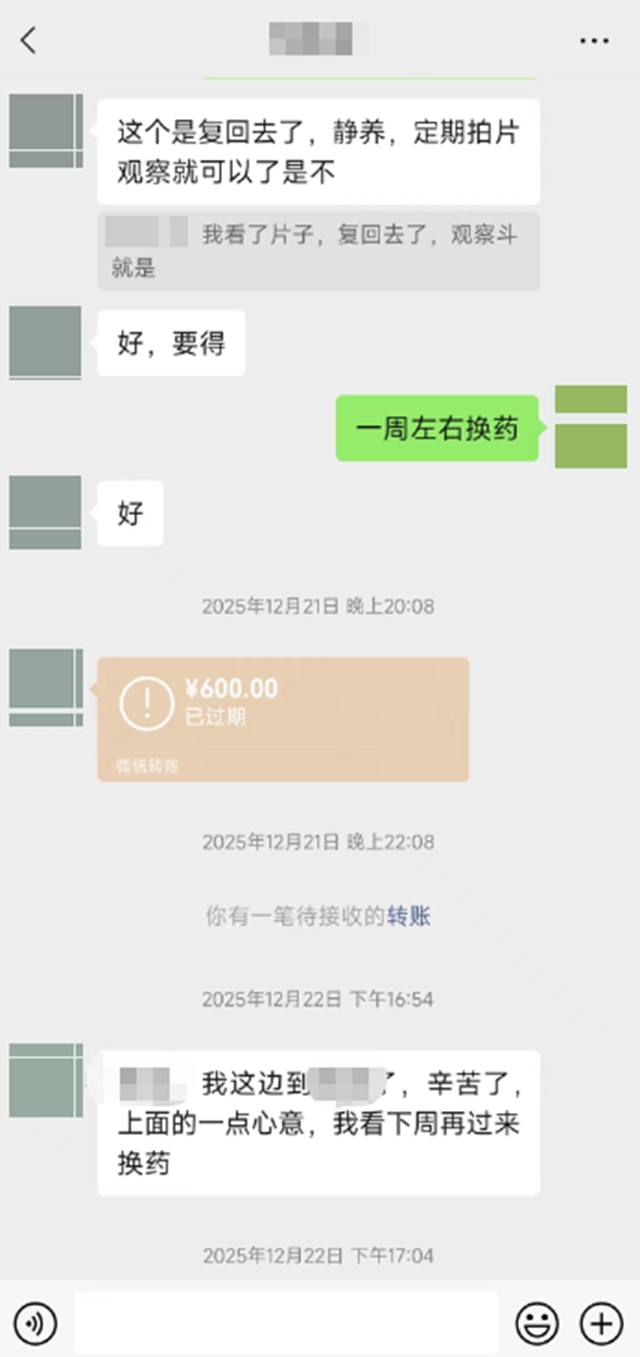

看着自己的手逐渐康复,没有留下任何疤痕,小杨暗自庆幸当时没有手术,心理满是感激。他特意找到江锋和王念武医生,通过微信转账发红包,想要表达自己的谢意,可没想到二位医生当场就拒收了。

“你选择相信我们,医生也必定全力以赴,心意已领,红包绝对不能收。”江锋医生的一句话,让小杨心里暖暖的。